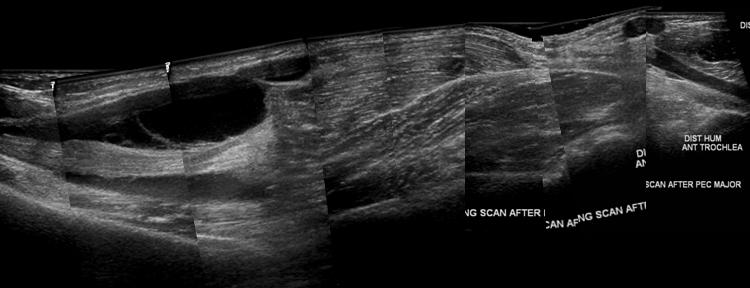

the Pectoralis Major. After the

surgical neck, the Peck Major

inserts to the humerus, when

large muscle belly tear occur,

fluid build up usually begins

here and traces distally.